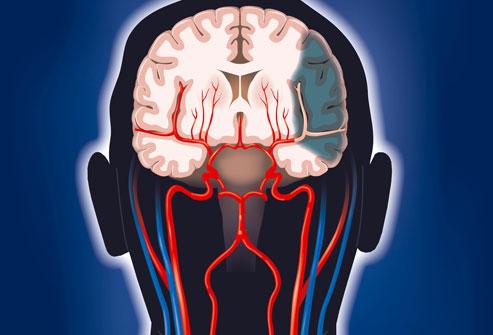

腦梗是一種常見的腦血管疾病,具有高發(fā)病率、高致殘率和高死亡率的特點,腦梗是指局部腦組織因血液循環(huán)障礙,導致缺血、缺氧而發(fā)生的軟化壞死,本文將詳細介紹腦梗的各個方面,幫助讀者更好地認識這一疾病。

腦梗的定義

腦梗,即腦梗死,是一種由于腦部血液供應障礙導致的局部腦組織缺血、缺氧,進而引起腦組織軟化及壞死,腦梗可分為腦血栓形成、腦栓塞和腔隙性梗死等多種類型。